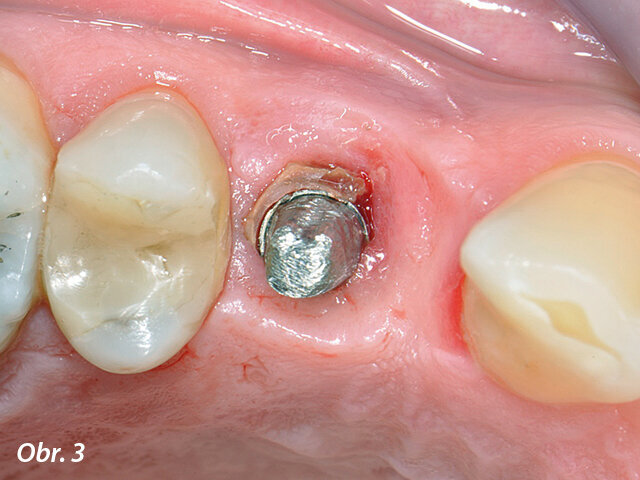

Periimplantitidou postižený implantát v pozici zubu 14 s patrnou patologickou hloubkou sondáže: a) implantát opatřený korunkou

Periimplantitidou postižený implantát v pozici zubu 14 s patrnou patologickou hloubkou sondáže: b) stav po sejmutí korunky